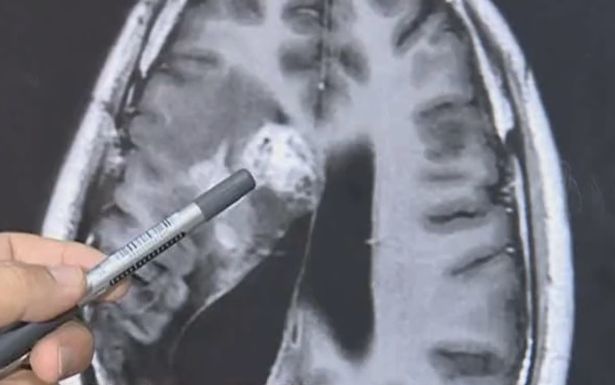

Ảnh chụp CT não của Wang.

Năm 2018, các bác sĩ phát hiện một con sán sống trong não bệnh nhân. Ở thời điểm đó, các bác sĩ chỉ định biện pháp chữa trị không phẫu thuật vì ký sinh trùng nằm ở khu vực nhạy cảm, rất khó phẫu thuật.

Đến nay, sán dây vẫn sống trong não Wang nên các bác sĩ ở bệnh viện tỉnh Quảng Đông phải phẫu thuật mở hộp sọ. Ca phẫu thuật kéo dài 2 giờ kết thúc tốt đẹp khi các bác sĩ gắp được con sán dây, chủ yếu ký sinh ở chó mèo, ra ngoài.

Bác sĩ làm phẫu thuật gắp con sán dây ra khỏi nao bệnh nhân.

Bác sĩ Gu nói với truyền thông địa phương: “Ca phẫu thuật rất nguy hiểm. Sán dây không ngừng di chuyển trong não bệnh nhân, nhưng nếu không phẫu thuật, nó có thể đe dọa tính mạng bệnh nhân”.

Bác sĩ Gu nói đây là lần thứ 4 ông chữa cho bệnh nhân nhiễm sán dây. “Mọi người nên cẩn thận khi nấu thịt ếch, ốc và rắn vì nếu không nấu chín, sán dây vẫn còn sống”, bác sĩ Gu nói. “Và không được uống nước chưa đun sôi”.